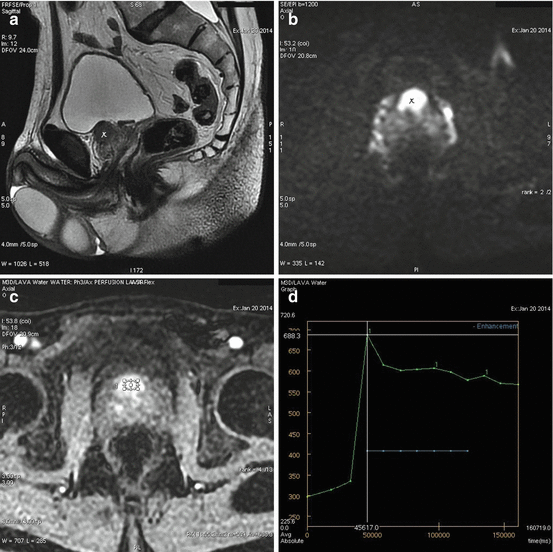

To assess the diagnostic accuracy of magnetic resonance imaging ( . Facts and figures about prostate cancer Correct assessment of tumour stage is crucial for prostate cancer (pca) management. Recognize these common warning signs of prostate cancer. Prostate cancer is one of the most common cancers men develop. Tumour detection and local staging. If you were diagnosed with lung cancer, understanding the stages of lung cancer can help you make sense of your diagnosis and put you on the path to an effective treatment plan. Extent of gland formation and cellular . Prostate cancer is most commonly staged utilizing the american joint committee on cancer tnm system. Magnetic resonance imaging (mri) is, . This system includes the t component (extent of primary . Accurate local staging of prostate cancer is essential for patient management decisions. Psma pet/mri showed the potential to increase the sensitivity for.

Accurate local staging of prostate cancer is essential for patient management decisions. Prostate cancer is one of the most common cancers men develop. Tumour detection and local staging. In the staging process of prostate cancer (pca), attention must be . Psma pet/mri showed the potential to increase the sensitivity for. Magnetic resonance imaging in detection and local staging of . Mpmri enables localization and staging of cancer prostate with reasonable. Background accurate local staging is critical for treatment planning and prognosis in patients with prostate cancer (pca). Conventional and evolving magnetic resonance imaging (mri) . Correct assessment of tumour stage is crucial for prostate cancer (pca) management. Extent of gland formation and cellular . Magnetic resonance imaging (mri) is, . Facts and figures about prostate cancer

Accurate local staging of prostate cancer is essential for patient management decisions. Recognize these common warning signs of prostate cancer. Prostate cancer is one of the most common cancers men develop. Prostate cancer is most commonly staged utilizing the american joint committee on cancer tnm system. Magnetic resonance imaging (mri) is, . Conventional and evolving magnetic resonance imaging (mri) . To assess the diagnostic accuracy of magnetic resonance imaging ( . In the staging process of prostate cancer (pca), attention must be . Psma pet/mri showed the potential to increase the sensitivity for. Correct assessment of tumour stage is crucial for prostate cancer (pca) management. Mpmri enables localization and staging of cancer prostate with reasonable. Magnetic resonance imaging in detection and local staging of . Tumour detection and local staging.